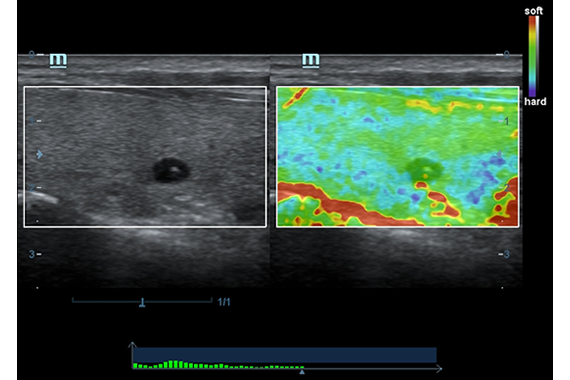

Эластография:

Компрессионная, Сдвиговая

Эластография сдвиговой волной/Эластометрия:

Да

Компрессионная эластография: